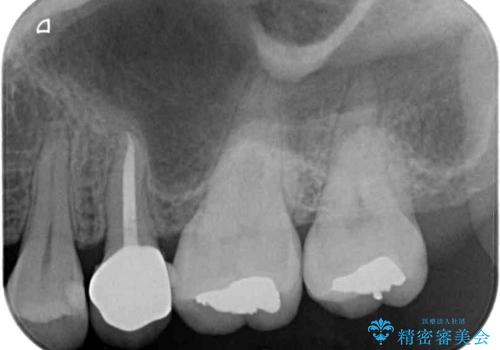

- 近医にてむし歯治療を行った後に痛みが出たとのことで来院された患者様です。

左下奥歯は術後から咬合時の痛みが発現し、来院時には脈を打つような痛みが認められました。

診察の結果、神経を取り除く必要があると判断されたため根管治療を行いました。

その後、左上の奥歯にも咬合時の痛みが認められ、レントゲン写真より歯内の神経が失活していることが分かりました。

2歯ともに根管治療を行い、その後はオールセラミッククラウンにて補綴治療を行うこととしました。